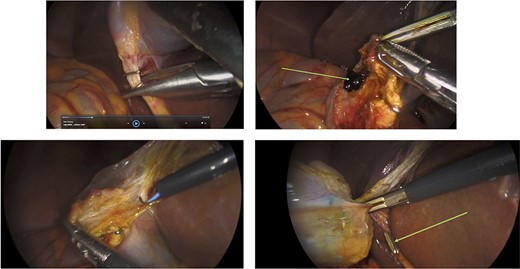

Surgery: laparoscopic cholecystectomy. (a) clipping of the common bile duct. (b) retrograde dissection of the fundus of the gallbladder. (c) iatrogenic gallbladder injury and spillage of pigment stones (green arrow). (d) completion of the retrograde dissection with visualization of the cystic duct stump (green arrow).